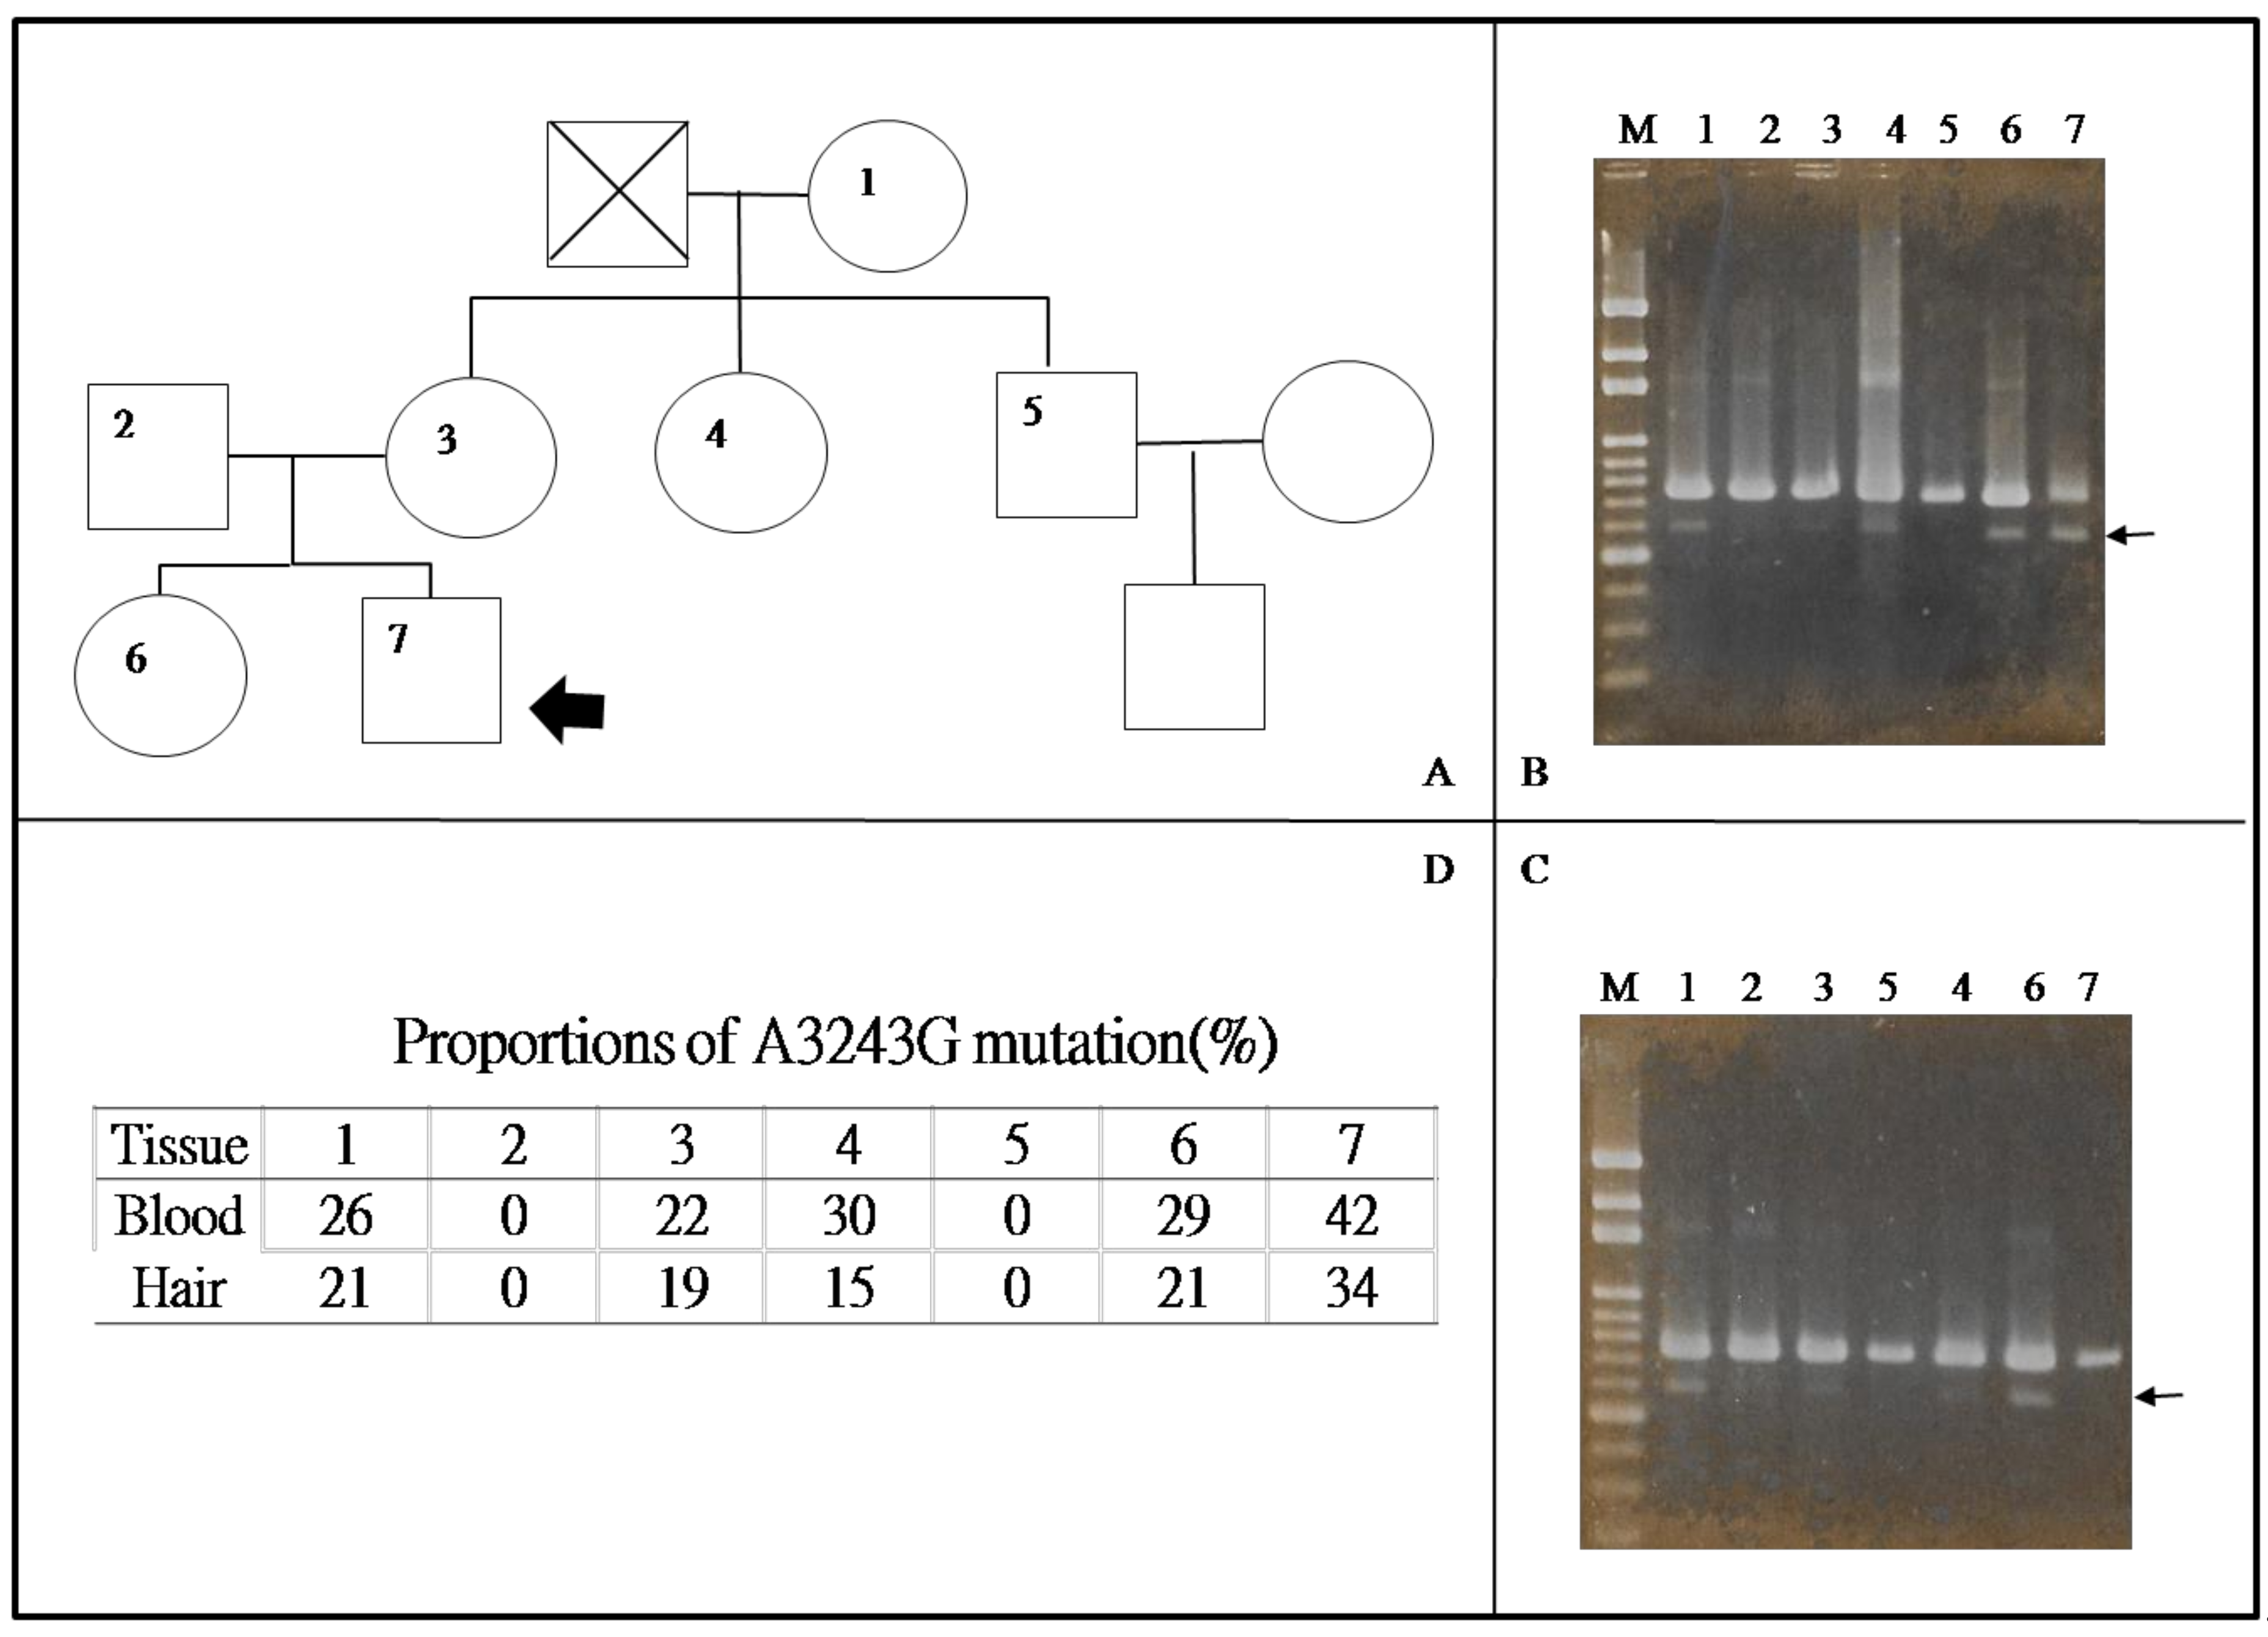

3.1. Genetics of MELAS Syndrome

4. Diagnosis